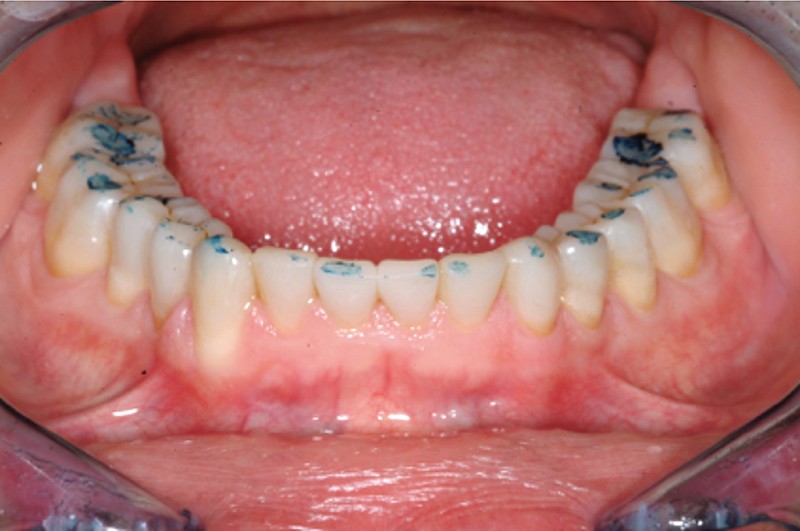

Jean-Pierre Attal : Exactement, car il est possible d’appliquer le protocole de la technique « 3 steps » aux patients présentant des pertes de substance d’origine attritive (bruxisme) (fig. 5).